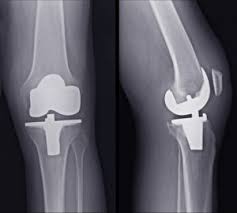

The company ORTHOPEDIC NIKIFOROV was founded in 1998 by the candidate of medical sciences. doctor of orthopedic-traumatologist of the highest category Nikiforov IA Owing to high professionalism and results of work, ORTONIC has gained well-deserved reputation and reputation among colleagues and population of Dnepropetrovsk region and CIS countries (Russia, Moldova, Armenia, etc.). The principle of the enterprise is NO IMPOSSIBLE, it is based on knowledge, experience and active implementation of modern technologies in orthopedics and traumatology. Conservative methods of treatment include individual selection of medicines, therapeutic blockades, manual therapy, massage, physiotherapy (vibration table, magnetotherapy, bioptron, electromyostimulation, etc.), rehabilitation with the suggestion of the necessary concomitant devices and means for the fastest recovery (corsets, bandages, various joint fixators, crutches, walking sticks, etc.). Various minor invasive interventions (chymonucleolysis, vertebroplasty, kyphoplasty, percutaneous nucleoplasty using cold plasma) that are performed on an outpatient basis are successfully used to treat problems associated with spine pathology. The latest modern treatment methods introduced in our company are endoscopic operations using the TYSSES technique of Joimax (Germany) with intervertebral hernias, stenosis and other pathologies of the spine, which allow to avoid complications occurring during open operations and the accompanying general anesthesia. We have many years of successful experience in traditional and modern minimally invasive endoprosthetics of large and small joints, which remains the main direction of our activity. Our company is the exclusive representative of the German company IO International Orthopaedics Holding GmbH, which based on the already known prostheses, its ideas and technological capabilities, has developed and implemented a new concept in hip replacement - an artificial joint prosthesis (ICON). We assist interested colleagues in training the operative technique for installing an artificial joint prosthesis - ICON, both in the workplace and in Germany. For 20 years we have been successfully cooperating with Sanitatshaus Gerd Klinz ortho team, an enterprise that for 20 years has been one of the leading places in Germany for the production of functional prostheses of the upper and lower limbs, as well as cosmetic prostheses of limbs and other body parts (nose, ears, eyeballs, fingers). We have an atmosphere of friendliness and human participation. Politeness, benevolence, the desire to understand and help is the basis of our attitude towards patients. We are always glad to see you and will do our best to make you feel great! We are waiting for you at: Ukraine, Dnepr, Gagarin Ave., 13 (under reconstruction) on all questions to address: tel .: +38 (050) 488-88-92 E-mail: orthonik.ukr@gmail.com Germany, Spine Nano Klinik, Zeppelinstr. 21, Potsdam Tel. +4901801121919 E-mail: kmw.nikiforov@hotmail.de